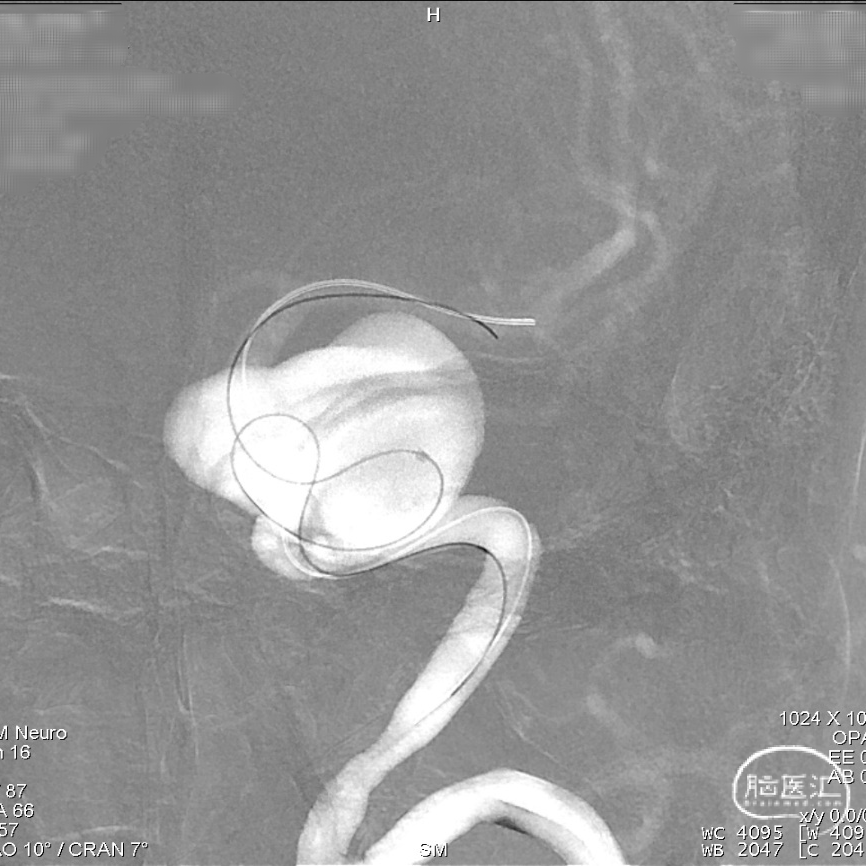

导丝按摩:

为防止支架未完全贴壁,即刻采用“massage技术”从远至近对Tubridge血流导向密网支架每个节段进行充分按摩。

术后即刻造影显示,支架打开良好、贴壁充分,囊内有明显的滞留。

治疗体会

血流导向密网支架作为治疗大/巨大型颅内动脉瘤各文献中明确确定了它的疗效价值,本病例我们首选采用血流导向密网支架为患者进行治疗。在本次使用Tubridge血流导向密网支架(改进版)治疗颈内动脉巨大动脉瘤过程中,支架头端锚定精准、打开顺利,Tubridge(改进版)良好的通过性和支架的充分贴壁确保了手术治疗的安全性。